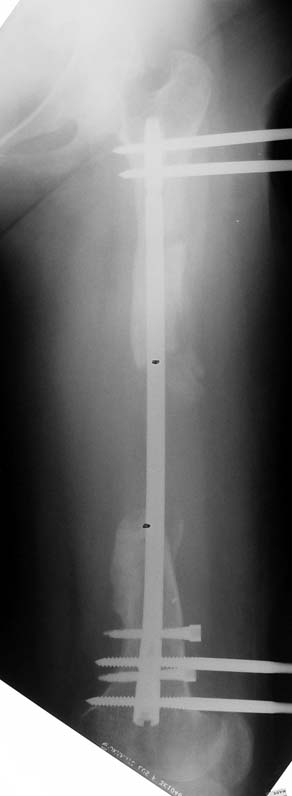

3. POSTTRAUMATIC LOWER LIMB SHORTNESS (MALUNION)

This type of shortness occurs after a fracture heals in a shortened position. Most cases are seen in adults and can be treated with one lengthening operation. Additional deformities can be corrected simultaneously. Most of these cases can be treated with lengthening over nail or just corrections and intramedullary nailing.